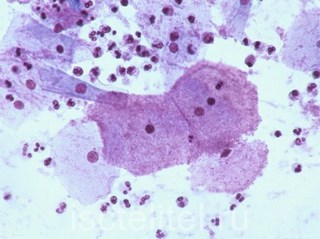

Для диагностики заболевания существует несколько методов, но самым точным из них, позволяющим определить не только наличие возбудителя, но и его численность, является влагалищный мазок. Так же возможно назначение анализа на микрофлору и общего анализа крови. Гарднереллез может оказаться безобидным признаком венерологических заболеваний, поэтому часто дополнительно назначают обследования на сопутствующие инфекции.